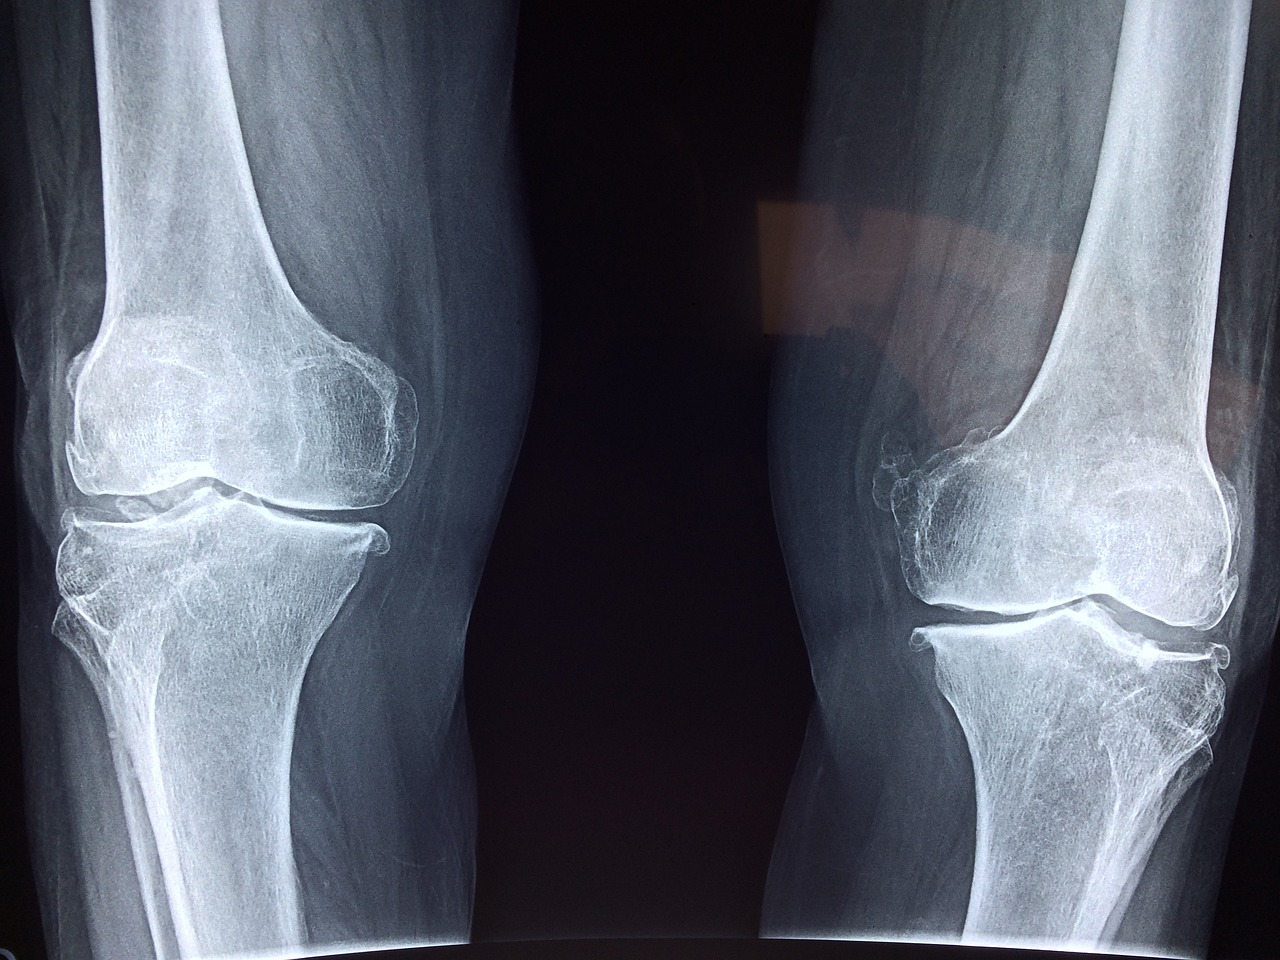

- 글루코사민 & 콘드로이틴

- 연골을 형성하는 성분으로, 관절의 윤활 작용을 돕고 연골 손상을 예방합니다.

- 특히 퇴행성 관절염 예방과 통증 완화에 효과적입니다.